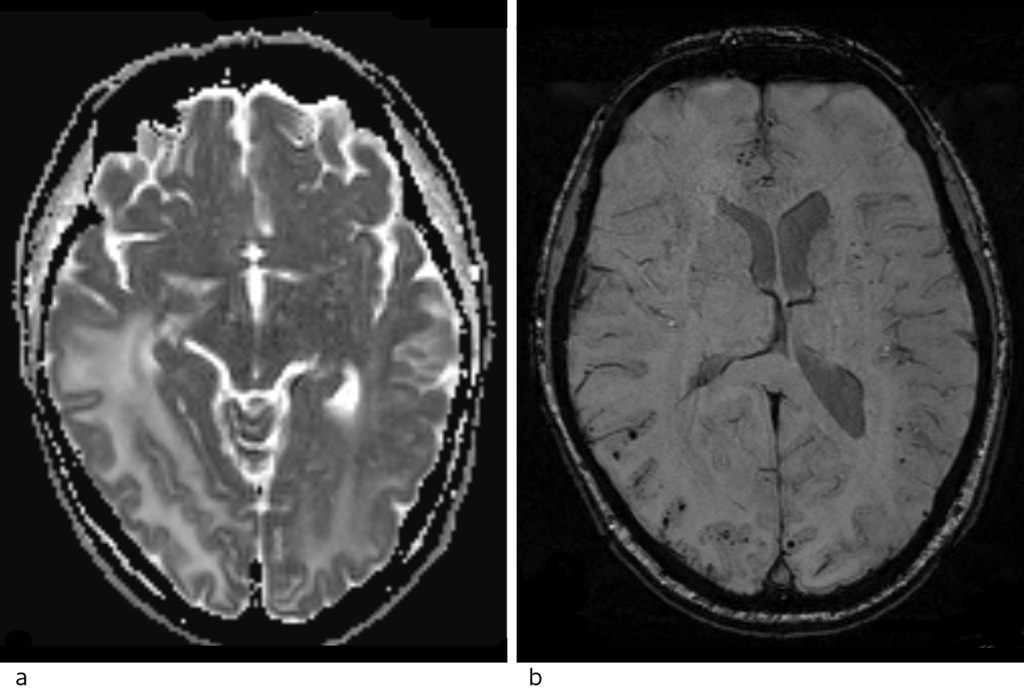

The MRI with intravenous contrast (Fig. 2) showed increased signal in the white matter in the right temporal and occipital regions, and in the medial left occipital region on T2 weighted and FLAIR sequences. There was no restriction on a diffusion-weighted series (as usually seen in stroke, abscess and tumours), but an increased apparent diffusion coefficient (ADC), consistent with vasogenic oedema. There was no pathological contrast enhancement or contrast-enhanced lesions, which would point to metastases, abscess or primary brain tumour, but numerous punctate haemorrhages were seen in the cortex of the corresponding areas on susceptibility-weighted sequence. MRI spectroscopy showed normal metabolite distribution, which also weighed against tumour.

Figure 2 Head MRI. a) ADC map with high values consistent with vasogenic oedema. b) Susceptibility-weighted imaging (SWI)…

Figure 2 Head MRI. a) ADC map with high values consistent with vasogenic oedema. b) Susceptibility-weighted imaging (SWI) shows numerous punctate lesions with a very low signal, consistent with microhaemorrhages spread through the cortex of both hemispheres, predominantly in the right occipital lobe.